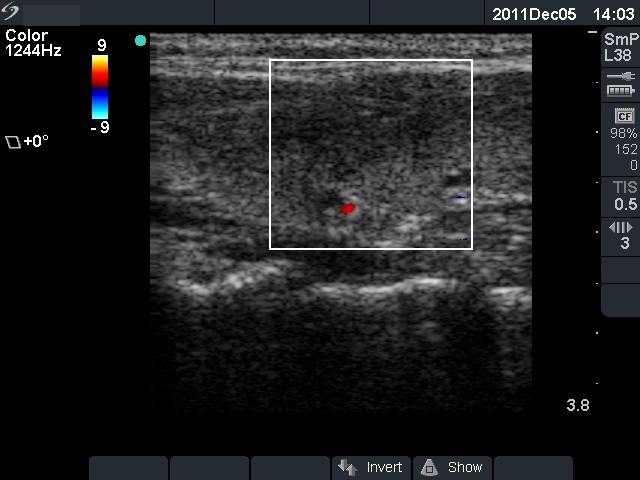

Initial examination (first row of images):

Clinical presentation: A 29-year-old woman requested a second opinion. She was in the 11th week of her pregnancy. She had mild neck discomfort for 2 months. A suspicious nodule was found in the left lobe on the evaluation. Aspiration cytology was repeatedly non-diagnostic. She was told that she had thyroid carcinoma with great probability. Her endocrinologist recommended to abort the child and then to undergo thyroidectomy.

Palpation: The left thyroid was hard on palpation, but not painful.

Ultrasonography: The right thyroid was echonormal and contained several small, insignificant lesions. There was a hypoechogenic lesion with blurred borders in the central and in the ventro-medial part of the left thyroid with increased intranodular blood flow.

Aspiration cytology resulted in thyroiditis, not otherwise specified.

Laboratory tests: subclinical hyperthyroidism. Serum-calcitonin, anti-TPO, anti-hTg, TSAb resulted in normal values.

Combined clinical-sonographic-cytological diagnosis: subacute, de Quervain's thyroiditis.